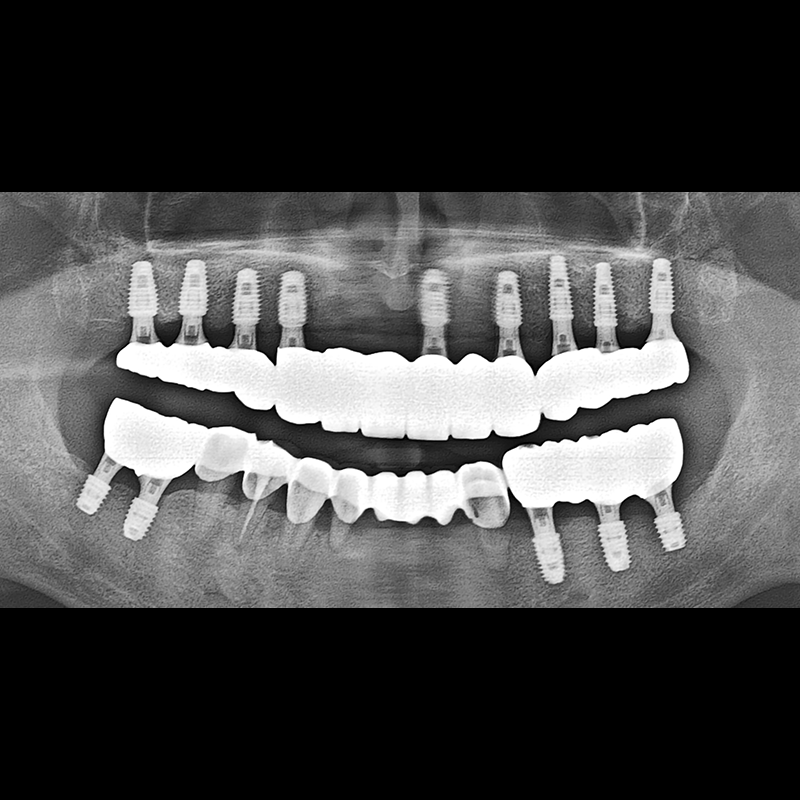

IMPLANT

BEFORE AFTER